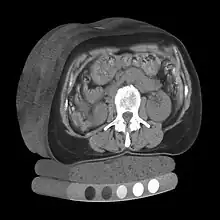

Tomography is imaging by sections or sectioning that uses any kind of penetrating wave. The method is used in radiology, archaeology, biology, atmospheric science, geophysics, oceanography, plasma physics, materials science, cosmochemistry, astrophysics, quantum information, and other areas of science. The word tomography is derived from Ancient Greek τόμος tomos, "slice, section" and γράφω graphō, "to write" or, in this context as well, "to describe." A device used in tomography is called a tomograph, while the image produced is a tomogram.

In many cases, the production of these images is based on the mathematical procedure tomographic reconstruction, such as X-ray computed tomography technically being produced from multiple projectional radiographs. Many different reconstruction algorithms exist. Most algorithms fall into one of two categories: filtered back projection (FBP) and iterative reconstruction (IR). These procedures give inexact results: they represent a compromise between accuracy and computation time required. FBP demands fewer computational resources, while IR generally produces fewer artifacts (errors in the reconstruction) at a higher computing cost.[1]

Volume rendering is a set of techniques used to display a 2D projection of a 3D discretely sampled data set, typically a 3D scalar field. A typical 3D data set is a group of 2D slice images acquired, for example, by a CT, MRI, or MicroCT scanner. These are usually acquired in a regular pattern (e.g., one slice every millimeter) and usually have a regular number of image pixels in a regular pattern. This is an example of a regular volumetric grid, with each volume element, or voxel represented by a single value that is obtained by sampling the immediate area surrounding the voxel.